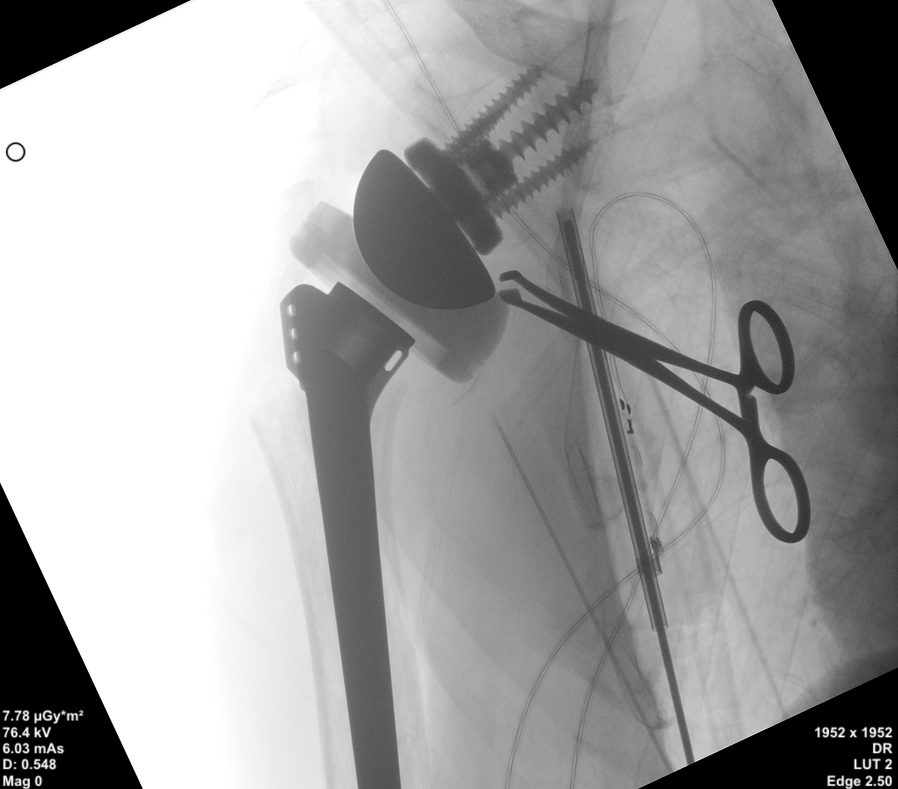

术中,导针精准植入。

在导针的精准定位后,为患者置入肩盂侧假体组件,以及后续肱骨侧假体组件,顺利完成手术。手术共计耗时2小时,出血不到200ml,术后复查X片也显示假体植入位置非常满意。

肩盂侧假体组件及后续肱骨侧假体组件置入。